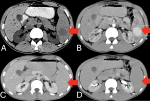

A 21-year-old male residing in the Southeast Asia region presented to the emergency department with intermittent left upper quadrant pain and mild fatigue lasting for several weeks with vague complaints of fever with 3-4 episodes of loose stool and multiple episodes of vomiting. He had no significant past medical history and was not on any medications. Physical examination revealed mild tenderness in the left upper quadrant but no palpable mass. He was advised a contrast-enhanced computed tomography (CECT) examination which revealed hyperdense (A) enhancing lesion noted at lower pole of spleen which is enhancing in arterial (B) phase with rapid washout on portal (C) and delayed phase (D). The lesion is noted to get arterial feed from splenic artery, suggestive of splenic hamartomas. Splenic hamartomas are very rare lesions commonly found incidentally on imaging. They are most often solitary but may be present as multiple nodules in patients with tuberous sclerosis or Wiskott-Aldrich syndrome. Splenic hamartomas are very rare, with only 3 described in a series of 200,000 splenectomies. Hamartomas are normally incidental findings at imaging, surgery, or autopsy. They can occur in any age group. Symptoms occur from mass effect if they grow large. Splenic hamartomas may not require surgical intervention unless they are large or symptomatic. Imaging characteristics can be misleading, and histopathological examination remains the gold standard for diagnosis. In this case, the patient's symptoms were attributed to the hamartoma, which was successfully managed with splenectomy.

Figure 1: contrast enhanced computed tomography image of abdomen in axial section showing hyperdense (A); enhancing lesion noted at lower pole of spleen which is enhancing in arterial (B); phase with rapid washout on portal (C) and delayed phase (D) suggestive of splenic hamartoma